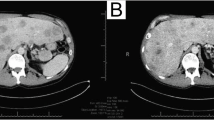

The patient was a 5-year-old Japanese girl who was the second child of nonconsanguineous healthy parents. At 26 weeks of gestation, she was diagnosed with left pleural effusion and fetal hydrops by ultrasonography, and pleural drainage was performed. She was delivered by emergency cesarean section at 33 weeks of gestation because of increasing fetal hydrops. Her Apgar score was 5 (1 min)/7 (5 min), and her birth weight was 2604 g (> 97th percentile). She showed scattered capillary malformations in the upper and lower lips and both upper and lower limbs and enlargement of both second toes at birth. At 5 years, she was referred to our outpatient department. At that time, she showed systemic lipomatous overgrowth, particularly in the thorax and legs. Ultrasonography revealed lipomatous overgrowth and no development of mammary gland tissue. Scoliosis was observed by spinal X-ray examination (Fig. 1a). Enlargement of both second toes was still observed. Brain magnetic resonance imaging showed no abnormality, and she had no developmental disorders. Accordingly, we considered a diagnosis of CLOVES syndrome. Abdominal ultrasonography showed pancreatic hyperechogenicity (Fig. 1b), indicating PS. Her hemoglobin A1c (HbA1c) was elevated (6.1%). Her height at 5 years of age was 108.6 cm (− 0.7SD), and her body weight was 21.9 kg (body mass index, 18.6).

a Chest radiograph of the patient showed scoliosis. b Ultrasonography showed a hyperechogenic pancreas (white arrow). c Results of PIK3CA gene analysis by Sanger sequencing. Identification of a mosaic missense variant of PIK3CA (c.1357G>A causing p.Glu453Lys) in DNA derived from skin fibroblasts; no variant was observed in DNA derived from peripheral blood